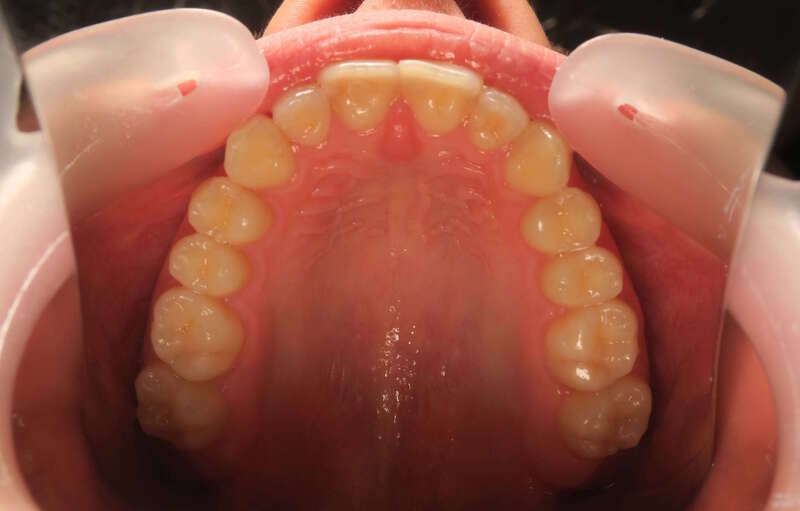

Cas n°1 traité par aligneurs (interception) - enfant

Ce cas d’interception chez un enfant de 8 ans démontre l'efficacité des aligneurs pour corriger des troubles fonctionnels précoces. Le diagnostic présentait des inversions d'articulé provoquant une déviation de la mandibule vers la gauche et un décalage des milieux.

Grâce à une coopération exemplaire et un traitement totalement indolore, l'expansion de l'arcade a permis de recentrer la mâchoire. Cette intervention a littéralement remis la croissance sur les rails, neutralisant le risque d'asymétrie faciale squelettique.

• Correction fonctionnelle : Recentrage immédiat de la mandibule et des milieux inter-incisifs.

• Prévention : Création d'un environnement favorable pour les dents définitives à venir.

• Bien-être : Approche douce respectant le confort de l'enfant.

C'est une étape fondamentale qui simplifie l'avenir orthodontique du patient tout en garantissant un développement facial harmonieux.

Avant

Après